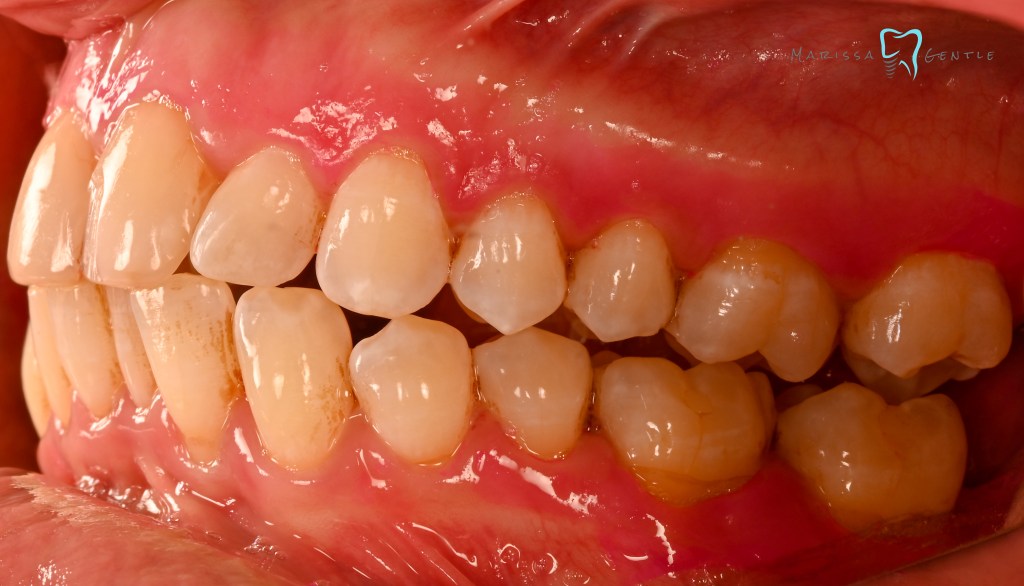

Patient presented with esthetic concern, composite veneers were placed 3 years prior. Patient’s chief complaint is twisted #7, thickness of the composite veneers and now chipping. The veneers were placed initially due to Enamel hypoplasia. Clinically relevant information: the patient wears a mandibular advancement device as treatment for sleep apnea, malocclusion noted edge to edge. Zirconia crowns planned #7-10

Current composite veneers are defective and caries are clinically present